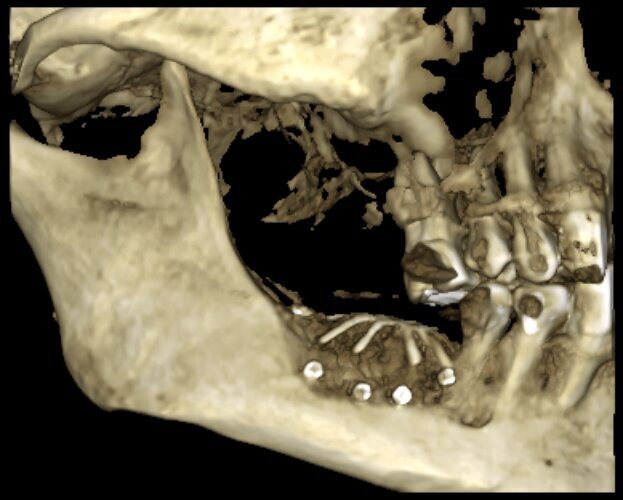

Figg. 1, 2_L’immagine clinica preoperatoria pone in evidenza un ampio difetto osseo sia orizzontale che verticale.